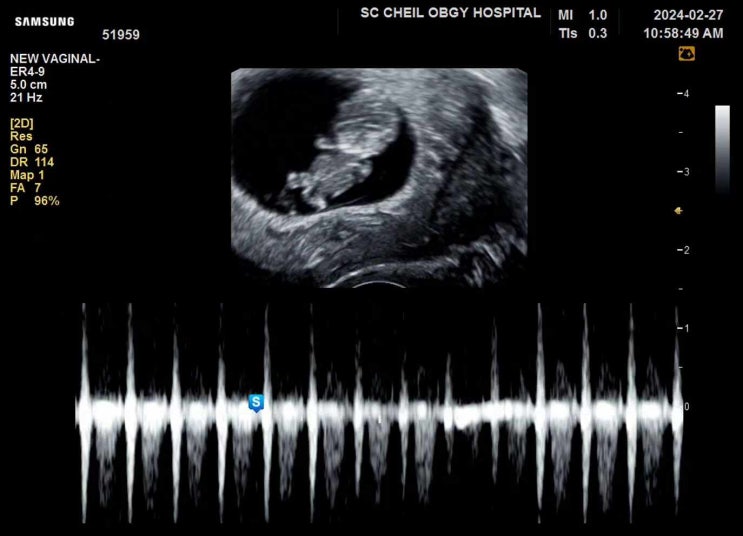

임신기록ㅣ 9w

젤리곰을 보러 병원에 다녀왔다 !? 내 뱃속에서 아기가 잘자라고있는지 불안하긴했지만 먹덧과 컨디션이...